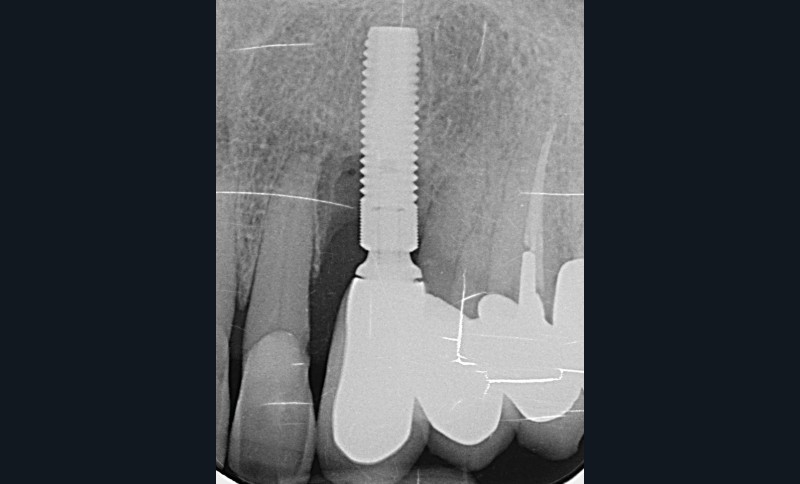

L’implant

- Site 23

- Mis en place il y a 12 ans